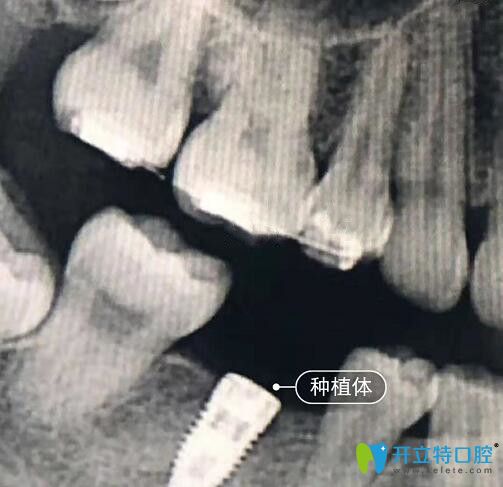

我在<!--<i data=20240703-sp></i>-->億大口腔做種植牙CT片

億大口腔的張睿醫(yī)生不愧是原的種植醫(yī)生,種植牙技術(shù)確實(shí)不錯(cuò),而且服務(wù)也很貼心,術(shù)后會(huì)定期回訪、提醒復(fù)診等。所以,還在糾結(jié)“種植牙哪家醫(yī)院好?”的朋友們,可以到億大口腔體驗(yàn),既能享受到與醫(yī)生同步的技術(shù),還免去了排隊(duì)的麻煩!